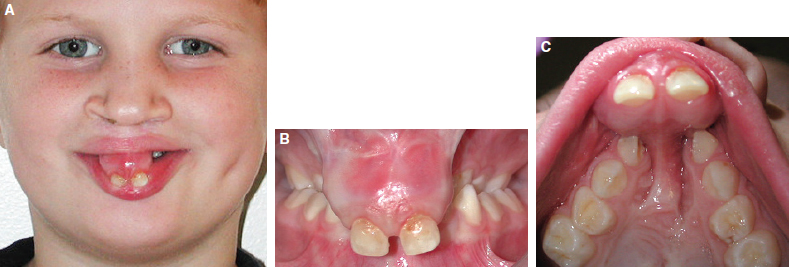

65 ○ The interdisciplinary team approach was developed to provide efficient and effective integrated care for the timing and management of infants born with orofacial clefts and craniofacial anomalies. ○ The orthodontist’s role has traditionally included considerations of both skeletal and dental growth and development. ○ Management of the postnatal growth of the nasomaxillary and mandibular components has been conveniently divided and integrated into four developmental stages: neonatal maxillary orthopedics, the primary dentition, the mixed dentition, and the adolescent and adult permanent dentition. ○ The timing and sequencing of alveolar bone grafts during the mixed dentition stage and orthognathic surgery during the permanent dentition stage require close collaboration of the orthodontist with the surgeon. ○ If skeletal malocclusion is severe in the primary or early mixed dentition, skeletal correction should be delayed until the permanent dentition stage, when a combined approach of comprehensive orthodontics and orthognathic surgery may lead to a more predictable correction. ○ The maxillary incisors adjacent to the cleft site may be tipped, rotated, malformed, or hypoplastic with an absence of bone in the cleft site to support the eruption of the permanent lateral and canine teeth. ○ Orthodontic alignment of maxillary incisors before secondary bone grafting must be limited by the available bone into which the teeth can be moved. ○ In patients with a missing maxillary lateral incisor at the cleft site, the edentulous space can be closed by prosthetic replacement of the lateral tooth (with a fixed partial denture or an endosseus implant) or by orthodontic mesialization of the canine tooth (canine substitution). The document “Parameters for Evaluation and Treatment of Patients with Cleft Lip/Palate or Other Craniofacial Anomalies,” developed by the ACPA in 19921 and later revised in 2009,2 has provided clinicians and third-party payers with guidelines to the scope, timing, and sequencing of treatment for patients with cleft lip or palate. Within the document, the role of the orthodontist is well defined, noting that this role should be a collaborative effort with other dental, medical, and allied health professionals. Emphasis is given to the monitoring of craniofacial growth and development and to providing treatment when necessary to achieve optimal function and appearance. Delivery of orthodontic treatment is recommended in discrete stages of the skeletodental development of the craniofacial complex to prevent continuous treatment from the early mixed dentition to the permanent dentition. These concepts are further explained in texts outlining the role of the orthodontist in the management of cleft lip and palate.3,4 The purpose of this chapter is to discuss the orthodontic principles that govern the contemporary management of patients with an orofacial cleft, from diagnostic considerations to issues of timing and sequencing of treatment. The team approach to the comprehensive care of children born with orofacial clefts requires collaboration among the orthodontist and the other members of the team (Fig. 65-1). The timing and sequencing of orthodontic care requires prioritizing each patient’s other health care needs in the context of an integrated treatment plan derived from a consensus of all team members. Orthodontic interventions may be conveniently divided into four distinct periods defined by age and dental development: neonatal period, primary dentition, mixed dentition, and permanent dentition. Neonatal (or infant) orthopedics occurs during the early postnatal period, usually in the first few months after birth, unless contraindicated by other medical conditions. This intervention was introduced in the 1960s by Burston5 and McNeil6 with the intention that early alignment of the maxillary segments would subsequently allow the dentition to erupt into a more normal occlusion and eliminate the need for orthodontic correction. As this intervention gained popularity, the complexity of the appliances used increased, with both intraoral and extraoral components. The least invasive technique was simple extraoral lip taping (Fig. 65-2). Fig. 65-2 An infant with a complete unilateral left cleft lip and palate. A, Defect before orthopedic intervention. B, Presurgical orthopedics with lip taping to approximate the segments. C, Postsurgical result of definitive lip repair NAM involves an intraoral molding plate, nasal stents, and extraoral taping.7,8 Intraorally, the alveolar ridges are molded to reduce the width of the cleft, achieving approximation of the segments to within 1 to 2 mm of each other. Extraorally, the simultaneous use of nasal stents and taping allows for lengthening of the columella and reshaping of the lower lateral alar cartilages in both bilateral and unilateral clefts. This orthopedic treatment prepares the infant for a one-stage primary lip-nose repair in combination with a gingivoperiosteoplasty to close the alveolar defect. The lengthening of the columella that is achieved from NAM may eliminate or reduce future surgical procedures for columellar lengthening. Because these clinical interventions are performed early in the neonatal period, longitudinal follow-up into adolescence is necessary to evaluate the long-term effects of these early interventions on subsequent nasomaxillary growth. Inspired by the Eurocleft retrospective intercenter project of the 1990s and with advances in clinical outcomes trial methodology, the Dutch intercenter prospective two-arm randomized clinical trial (RCT), also known as Dutchcleft, was designed to study the outcome of neonatal maxillary orthopedics in subjects with unilateral cleft lip and palate (UCLP).9,10 Infant orthopedics in this trial consisted of the use of passive intraoral plates that were adjusted every 3 weeks to guide the maxillary segments and that were replaced with new plates as primary teeth emerged. In a 2005 study by Prahl et al,11 no significant difference could be found between the two randomized groups of infants up to 2 years of age with respect to feeding, nutritional status, or somatic growth. When assessing speech development at age 2.5 years, Konst et al12 found a significant improvement in children treated with infant orthopedics compared with children who did not receive infant orthopedics, with acceptable cost-effectiveness of the orthopedic treatment in regards to speech development. Further reports from the RCT indicated that infant orthopedics had no significant effect on various measures of maxillary arch dimension at ages 4 and 6 years when compared with similarly aged children who had not been treated with infant orthopedics.13 Similar findings were reported with respect to dental arch relationships at ages 4 and 6 years, including overjet, overbite, and sagittal occlusion.14 Cephalometric analyses of soft tissue, skeletal, and dental structures revealed only minor differences at age 6 years between the group treated with infant orthopedics and the untreated group.15 Facial appearance was also evaluated longitudinally in the two groups. Any group differences in facial appearance observed at age 4 years were no longer observed at age 6 years, at which time the better ratings in the infant orthopedic group could only be detected by professional raters.16 The Dutchcleft trial continues to monitor the patients longitudinally into their adolescence. In their conclusions, the investigators warned that clinicians who promote different methods of infant orthopedics, including NAM, should evaluate the long-term effects of their interventions using the rigorous methodology of an RCT.15 In their systematic review of the long-term effects of presurgical infant orthopedics, Uzel and Alparslan17 analyzed eight RCTs and four controlled clinical trials (CCTs), with follow-up periods of up to 6 years. Their results indicate that infant orthopedics has no positive effect on the treatment outcomes evaluated until the age of 6 years, including maternal satisfaction, feeding, speech, facial growth, maxillary arch dimension, occlusion, and nasolabial appearance. If neonatal orthopedics is recommended and feasible, it should be completed in the first few months of life so that definitive surgical lip repair can be achieved within the first 6 months. Palate repair is usually delayed until later in the first year of life. An ongoing controversy relates to the balance between the advantages of restoring the anatomy of the palate in the prelinguistic period and the effects of surgical scar tissue constraining the growth and development of the nasomaxillary complex. Ross18 evaluated the outcomes of both active and passive appliances in children with UCLP at age 10 years after neonatal presurgical infant orthopedics. The results in these groups were compared with those of untreated subjects at matched ages. This cephalometric study of facial growth in treated and untreated children with UCLP reported no beneficial long-term effect of neonatal orthopedics, although some negative effects were observed in those children who had received extraoral taping. As part of the Americleft intercenter study, Daskalogiannakis et al19 found that children with UCLP who were cared for at the only treatment center among the four participating North American treatment centers that did not employ any kind of infant presurgical orthopedics as part of their primary management protocol had the largest mean maxillary prominence (SNA angle) and maxillomandibular convexity (ANB angle) during the mixed dentition stage. None of the centers that provided infant orthopedics used NAM as their presurgical approach, but rather relied on extraoral taping with or without intraoral plates. Clearly, case-controlled studies are needed to establish the long-term effect of infant presurgical orthopedics on various outcomes including growth, dentoskeletal relationships, aesthetics, and socioemotional measures, among others. The primary dentition has usually fully erupted by the time the child is 2.5 to 3 years of age. At this age, the facial soft tissues may mask an underlying skeletal deficiency (Figs. 65-3 and Figs. 65-4). As the toddler grows into a young child, growth of the nasomaxillary complex lags behind that of the mandible, resulting in increasing midfacial deficiency. This may be reflected in the dentition as anterior or posterior crossbites. Patients with bilateral cleft lip and palate (BCLP) may have severe constriction of the posterior segments and protrusion or extrusion of the premaxillary segment (Fig. 65-5). The unilateral or bilateral crossbite may be associated with a functional mandibular shift, which is an early indicator for orthodontic treatment in the primary dentition. However, because the crossbite is likely to recur with the eruption of the permanent successors, a decision may be made to postpone orthodontic intervention until the mixed dentition. Fig. 65-3 A, A 6-year-old girl with repaired complete bilateral cleft lip and palate. B, Her mildly prominent maxilla. C, The primary dentition. D, The bilateral crossbite. E, A palatal fistula and primary laterals that erupted ectopically behind the premaxilla. Fig. 65-4 A, A 7-year-old boy with repaired complete unilateral left cleft lip and palate. B, His mild bimaxillary retrusion. C, The early mixed dentition period. Fig. 65-5 A 5-year-old boy with repaired complete bilateral cleft lip and palate. A, The severe extrusion of his premaxillary segment. B, The premaxillary segment out of the vertical plane of occlusion. C, The severe constriction of the posterior segments and extrusion of the premaxillary segment. Labial and palatal oronasal fistulas are present. Constriction of the dental arch is manifested in both the transverse and sagittal dimensions of the maxilla. Early skeletal midfacial deficiency has been addressed with some success if treated in the primary or early mixed dentition by a protraction face mask (Fig. 65-6). More recently, several studies have reported on the use of miniscrews, or temporary anchorage devices, to support the mandibular dentition while intermaxillary elastics are used to orthopedically protract the maxilla.20,21 Although the occlusal correction includes dentoalveolar proclination of the incisors, the modification and redirection of the skeletal mid-facial deficiency may be transitory. Continued growth restriction of the nasomaxillary complex results in failure to keep pace with normal mandibular growth. Consequently, malocclusion is often reestablished during the late mixed dentition and into the adolescent permanent dentition. Long-term follow up reveals biologic variability in response to the protraction facemask.22 The most logical time for the intervention is when the patient is younger than 10 years of age, during which time the circummaxillary sutures are more responsive. However, a severe malocclusion in the primary or early mixed dentition is unlikely to be corrected with growth modification, which may be a costly and unnecessary burden to the patient and result in questionable and often transient benefit. In such severe malocclusions, skeletal correction should be delayed until the permanent dentition stage, at which time comprehensive orthodontics in combination with orthognathic surgery or maxillary distraction may be more predictably reliable options. Fig. 65-6 An 8-year-old boy with repaired complete unilateral right cleft lip and palate with sagittal and transverse maxillary deficiency. A, The lateral radiograph showed 7 mm reverse overjet. B, Protraction facemask with elastics attached to palatal hooks on expander. C, Palatal expander with bands cemented on the maxillary second primary molars and canines, with palatal hooks to attach elastics. D, Lateral and anterior crossbites improved with palatal expansion and maxillary and dental protraction. E, Facial profile after 9 months of protraction facemask therapy and palatal expansion. F, Correction of anterior and posterior crossbite; the maxillary retainer is in place. G, Superimposition of initial and postprotraction lateral cephalogram tracings shows correction of reverse overjet by incisor proclination and mild maxillary advancement. (Black lines, initial profile at age 8 years; red lines, after 9 months of protraction facemask therapy.) Transition in the child’s dental development occurs between 6 and 12 years of age, as the primary dentition exfoliates and the permanent teeth erupt. Midfacial deficiency at this phase makes the mandible appear prognathic, thus resulting in a concave facial profile (Fig. 65-7). Eruption of the permanent teeth coincides with a period of psychosocial transition during preadolescence when the degree of friendship intimacy intensifies and independence from parents increases.23 Ward et al24 reported that the presence of an orofacial cleft decreases the oral health–related quality of life (OHRQoL) in children and adolescents. In preadolescents with craniofacial anomalies, dissatisfaction with appearance is related to social withdrawal, social anxiety, and self-consciousness.25 This is also the period during which the greatest advances have been made in restoring the bone in the cleft site through the use of secondary alveolar bone grafts, which improve the periodontal support of teeth adjacent to the cleft site and thus reduce or eliminate the need for extraction and prosthetic replacement of compromised teeth. The orofacial cleft disrupts the dental lamina in the cleft site so that the developing permanent teeth may be missing, malformed, or supernumerary. The incisors adjacent to the cleft site may be misplaced, rotated, malformed, or hypoplastic with an absence of necessary bone in the cleft site to support eruption of the permanent lateral incisor and canine (Fig. 65-8). Alveolar bone grafting restores the continuity of the alveolar ridge and allows for closure of oronasal fistulas. Transverse maxillary constriction may be the consequence of scar tissue formation after surgical repair of the secondary palate, resulting in a characteristic omega- or V-shaped arch form, reflected in anterior and posterior dental crossbites (Fig. 65-9). A maxillary expansion appliance is often recommended when the first permanent molars and incisors erupt. Collaboration between the surgeon and the orthodontist in the mixed dentition stage to coordinate the treatment sequence assists in achieving a successful alveolar bone graft with healthy adjacent teeth. Fig. 65-7 A, Same patient as in Fig. 65-4 at 9 years of age. B, The patient had a mild midface deficiency. C, An anterior crossbite was evident during this mixed dentition period. Fig. 65-9 A, The same patient as in Figs. 65-4 and 65-7, shown at age 9 years, with bilateral posterior and anterior crossbites. Note the severely rotated maxillary central incisor next to the cleft. B, The V-shaped arch form and palatal scarring. Primary alveolar bone grafting typically involves the placement of a bone graft in the neonatal cleft site at the time of primary surgical lip repair and hence before eruption of the primary incisors. Data suggests that this method may be deleterious to maxillary growth, so most cleft palate teams prefer to defer bone grafting until further maxillary growth and development has occurred.26 Secondary, or delayed, alveolar bone grafting is performed after primary lip repair and is classified according to the age at which the bone graft is placed: early secondary bone grafting (2 to 5 years), intermediate secondary bone grafting (6 to 15 years), or late secondary bone grafting (adolescence to adulthood). The principles of secondary bone grafting were first introduced by Boyne and Sands.27,28 In 1986, Bergland et al29 studied 378 consecutive patients who had undergone secondary alveolar bone grafting, showing that the best outcomes were achieved in patients in whom the bone graft was performed before the eruption of the maxillary canine. This report was followed by a cephalometric study that compared maxillary growth in children who received secondary alveolar bone grafting between the ages of 8 and 12 years with the maxillary growth in children who did not have a bone graft.30 There was no adverse effect of bone grafting on anteroposterior or vertical maxillary growth, a finding attributed to the postponement of grafting until most of the growth of the anterior maxilla had occurred and to the ability of the grafted bone to develop vertically with the alveolus.30 Since the publication of these landmark articles, current opinion supports the intermediate period as the most appropriate time for grafting. This practice has the greatest benefits and least risk for interfering with midfacial and skeletodental growth and development. Levitt et al31 demonstrated that there were no significant differences in maxillary sagittal or vertical growth after secondary bone grafting in patients with complete UCLP when compared with that in patients with similar clefts who did not receive a bone graft. The multicenter Eurocleft study of treatment outcomes in patients with complete cleft lip and palate compared craniofacial form in individuals treated at five European centers.32 The only center performing primary bone grafting obtained less favorable results in vertical maxillary growth, soft tissue sagittal relationships, and soft tissue facial proportions than the centers that performed secondary bone grafting between the ages of 8 and 11 years. Moreover, the center that used primary bone grafting obtained the least favorable dental arch relationships, with almost 50% of the patients needing surgical correction of maxillary retrusion at 17 years of age.33 In Americleft, the North American intercenter study of treatment outcomes in patients with complete UCLP, the only center performing primary bone grafting obtained the least favorable dental arch relationships, lowest maxillary prominence, and least favorable maxillomandibular relationships.19,34 Further justification for performing alveolar bone graft surgery during the mixed dentition period is that patients at this age are usually cooperative with the orthodontic procedures, such as maxillary expansion, that may be indicated before grafting.35 The donor site for graft harvest, typically the anterior iliac crest, has an acceptable volume of bone for successful grafting at this age.35 A survey of alveolar bone grafting practices among ACPA teams across North America revealed a consensus for the type of alveolar bone grafting performed: most of the centers perform intermediate secondary alveolar bone grafting.26 Therefore the following discussion focuses on alveolar bone grafting during this time period. A bone graft placed before eruption of the teeth adjacent to the cleft (especially the lateral incisor or canine when located on the posterior segment) provides a bony matrix to enable the eruption of these teeth into a continuous alveolar ridge, generating additional alveolar bone in the area29 (Fig. 65-10). Generally, grafting is done before the eruption of the permanent maxillary canine on the cleft side, which is usually located in the alveolar segment posterior to the cleft. Teeth directly adjacent to the cleft, particularly maxillary central or lateral incisors located on the proximal (mesial) segment, often erupt into unfavorable positions and may be ectopic, be rotated, or have an unfavorable axial inclination. This malposition is usually a reflection of the anatomy of the alveolar cleft, which is usually narrower at the alveolar margin and wider at the piriform aperture, thus limiting the amount of bony support for the teeth, especially along the root surface directly facing the cleft. Radiographs of these teeth often demonstrate a thin layer of cortical bone along their distal surface (see Fig. 65-10), bone that may be at risk for resorption if nonjudicious presurgical orthodontic uprighting is carried out. If a bone graft is placed before extensive orthodontic alignment of erupted teeth adjacent to the cleft, crestal bone heights are preserved, and postsurgical orthodontic alignment can be accomplished with minimal risk of bone resorption while ensuring adequate bony coverage of the roots. Oronasal fistulas can allow for nasal air escape with speech and may contribute to velopharyngeal dysfunction in patients with cleft lip and palate.36 A three-layered closure technique, with the graft interposed between the two soft tissue layers, yields a high success rate of fistula closure. Surgical closure of oronasal fistulas with secondary alveolar bone grafting often results in a significant improvement in speech, manifested as decreased nasality and nasal emission.37 Occasionally, large palatal fistulas cannot be closed at the time of alveolar bone grafting without compromising the integrity of the graft. On a case-by-case basis, surgeons may elect to close the palatal fistula in a separate surgical procedure, usually before alveolar bone grafting. Fig. 65-10 A, A bone defect at the cleft site in a 10-year-old patient before alveolar bone grafting. More than two thirds of the roots of the transposed lateral incisor and canine have developed (close to eruption). Note the thin layer of bone covering the adjacent central incisor. No orthodontic incisor alignment is planned. B, Periapical radiograph taken 4 months after alveolar bone grafting, showing excellent fill of the cleft defect with cancellous bone. The canine is erupting through the grafted bone. Alveolar bone grafting contributes to improved nasal and lip symmetry and provides a stable platform on which the nasal structures are supported.38 If performed alone or in combination with tip rhinoplasty (often as a separate procedure) alveolar bone grafting often yields aesthetic benefits. After a successful bone graft, the orthodontist can move the teeth bodily and upright roots into the cleft site without risk of compromising their periodontal support.29,39 The prosthodontist also can achieve a more aesthetic and hygienic prosthesis to replace missing teeth in the cleft area.39 Insertion of endosseous implants into the grafted cleft is possible and provides functional stimulation to the transplanted bone.40 Patients with bilateral clefts present with varying degrees of mobility of the premaxilla, which usually remains unstable throughout life.29 In such cases, secondary alveolar bone grafting stabilizes the premaxilla, allowing patients to have functional incisors with adequate stability to serve as abutments for fixed prostheses.29,39 The optimal time for performing secondary alveolar bone grafting can be established according to the age of the patient or, alternatively, according to dental development as defined by stage of root development. Chronologic Age By definition, secondary bone grafting is done during the mixed dentition stage, before the eruption of the maxillary canine (or lateral incisor, if located in the alveolar segment posterior to the cleft). Once teeth have erupted into the cleft site, their limited periodontal support will not improve with a graft, because the transplanted bone will not adhere to the tooth surface.35 The height of the crest of alveolar bone eventually resorbs to its original level. It is therefore essential to perform the graft before the eruption of the permanent teeth adjacent to the cleft. This period may encompass a range of several years, from age 6 to 15 years, when grafting has a high success rate. However, evidence shows that the older the patient is at the time of surgery, the poorer the outcomes of secondary bone grafting.41 Therefore the available evidence supports an optimum age at which patients should receive bone grafts. Using chronologic age alone for defining the optimal age for grafting may not be clinically valid, because patients with cleft lip or palate have delayed development of the teeth compared with individuals without clefts.42 Moreover, teeth adjacent to the cleft side demonstrate more developmental delay than the contralateral teeth.42 Dental development, based on assessment of the number of permanent teeth erupted and the extent of root formation, represents a more accurate indicator of the optimal timing for the bone grafting procedure than does chronologic age alone. Maxillary Canine Development One developmental indicator that has been proposed for establishing the optimal timing for grafting is the root formation of the permanent maxillary canine on the cleft side. It has been recommended that the optimal timing for secondary grafting is when the maxillary canine has developed one half to two thirds of its final length, which generally occurs between the ages of 8 and 11 years39,43 (see Fig. 65-10). This is advocated because when the root has developed two thirds of its expected full length, accelerated eruption of the canine occurs, and it can then erupt spontaneously through the graft, bringing additional alveolar bone into the area. In a retrospective study of patients with non-syndromic UCLP, Mercado et al44 demonstrated a significant positive correlation between stage of canine root development at the time of surgery and the outcome of bone grafting. Maxillary Lateral Incisor Development A study of patients with UCLP demonstrated that the cleft-side permanent lateral incisor was present in 50.2% of patients.45 Of these patients, 76.5% had the permanent lateral incisor located on the posterior segment, distal to the cleft. When the maxillary lateral incisor is located in the posterior segment, alveolar bone adjacent to the cleft is generally insufficient to support the lateral incisor as it drifts anteriorly and occlusally along its eruptive path into the arch. In such cases, grafting before the eruption of the lateral incisor may be advisable to improve the prognosis of this tooth.46,47 The developmental indicator of one half to two thirds of canine root formation for timing of an alveolar bone graft may be too late when the aim is to preserve an existing lateral incisor. Lilja et al48 discourage the use of root formation as an indicator for graft placement, proposing the assessment of the thickness of bone covering the crown (of the lateral incisor or canine) to determine timing of bone grafting. They advocate that bone grafting be performed when there is a thin layer of bone covering the tooth distal to the cleft. Other studies have reported no significant relationship between the degree of radiographic canine eruption through the alveolar cleft and the outcome of secondary bone grafting.49,50 The sequencing of procedures associated with placement of an alveolar bone graft requires interdisciplinary communication and cooperation for a successful outcome. Orthodontists, general or pediatric dentists, oral surgeons, and plastic surgeons intervene in a coordinated fashion to ensure that one discipline’s efforts do not interfere, delay, or jeopardize those of the other disciplines. Parents and caregivers may be concerned about teeth (often supernumerary) that have erupted near the cleft, either palatally or high in the labial vestibule. Ectopic teeth present a challenge for the parents and patient to maintain good hygiene because of their location and limited accessibility. The role of the general or pediatric dentist is to ensure that the patient and parents are aware of the ectopic teeth and that they are instructed on good oral hygiene practices to maintain the teeth free of decay, out of traumatic occlusion, and not contributing to traumatic ulcerations of the surrounding mucosa. The preservation of these teeth before surgery maintains the supporting alveolus. The general or pediatric dentist should restore any decayed teeth adjacent to the cleft before the grafting procedure. On the other hand, erupted teeth adjacent to the cleft that have poor periodontal or restorative prognosis should be extracted at least 2 months before surgery to allow the soft tissues to heal (see Fig. 65-8). This will allow healthy mucosal flaps to be reflected, positioned, and sutured over the grafted bone at the time of surgery. Healthy ectopic primary or supernumerary teeth that have erupted along the line of the cleft should also be removed at least 2 months before surgery to allow access to the surgical site. Orthodontic treatment may be required presurgically to reposition maxillary teeth that are in traumatic occlusion or to expand a severely constricted maxilla, thus providing the surgeon better access to the cleft defect. In bilateral cases, a mobile premaxilla with anterior traumatic occlusion may need to be addressed with a posterior bite plane to minimize mobility, which may compromise the success of the grafts during the healing period.35 A severely extruded premaxilla may need to be intruded to level it with the posterior segments (Fig. 65-11). This can be done with an active intrusion arch ligated over a passive segmental wire to the maxillary incisors. Alternatively, miniscrews placed directly on the premaxilla may serve as a point of attachment during intrusion, repositioning, and stabilization of the premaxilla.20 Other surgical procedures such as minor aesthetic revisions of the nose and lip, as well as the insertion of tympanostomy tubes, may be undertaken during the same general anesthesia setting of the alveolar bone graft. Dental prophylaxis and restorative work are generally not performed in conjunction with the bone grafting procedure to minimize the release of bacteria and debris into the surgical site. Unerupted teeth with poor prognosis adjacent to the cleft can be removed by the surgeon intraoperatively once the mucosal flaps have been reflected.